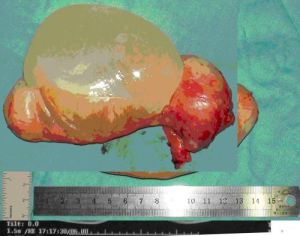

闌尾黏液囊腫闌尾黏液囊腫發病率低,起病緩慢,腹痛為隱痛,無急性感染時,症狀和體徵似慢性闌尾炎,常難以診斷,體積較大時可在體檢中發現完整、周圍無粘連的橢圓形腫物。且闌尾黏液囊腫由闌尾病變而來,易誤診為常見的闌尾膿腫,誤診率高達94.6%,本例CT掃描也出現上述情況。但CT及B超檢查仍是闌尾黏液囊腫術前與其他病變鑑別的重要手段。

闌尾黏液囊腫病例中,約有10%為惡性型,屬於真性腫瘤。囊腫破裂後可在腹膜上種植形成腹膜假黏液瘤。手術後容易復發,易發生腹腔種植等惡性行為,一般不發生淋巴及血行轉移,多數因腸梗阻或腎衰竭死亡。因此在手術中應特別注意防護,切除闌尾囊腫時應勿使其破裂,如果術中發現囊腫破裂,除切除闌尾黏液囊腫外,一定要徹底清洗腹腔,腹腔內可注入氟尿嘧啶,預防腹腔假黏液瘤的發生。